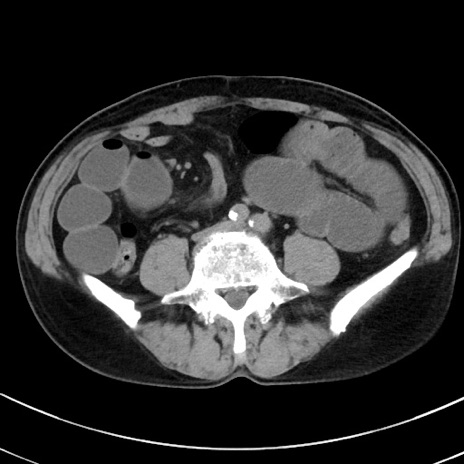

冠状断像

症例38(横断像)

【症例】70歳代 男性

【主訴】腹痛・嘔吐

【現病歴】昨晩より、嘔吐・腹痛あり。今朝になっても嘔吐あり。来院。

【既往歴】心臓バイパス手術、開腹胆摘、腸閉塞

【身体所見】BP 107/71mmHg、HR 116/min、腹部:平坦、軟、下腹部に軽度圧痛あり。反跳痛なし。

【データ】WBC 15100、CRP 0.32